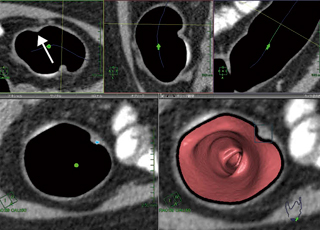

3. 直交カット断面にて解析を行う(図5)。このとき,仮想内視鏡画面を正面からカットし,オブリーク断面とほぼ同じ大きさの断面で処理を行う。また,大腸の断面の観察により,隆起病変とタギングされた残液の区別ができるため,クレンジング処理はOFFにする。観察中は仮想内視鏡画面,オブリーク断面,直交カット断面を同時に確認しながら,隆起があれば,“ポリープ確認”で抽出して観察し,CT値や大きさ,肛門からの距離などを記録保存する。このときの隆起病変のCT値は,約10〜80HUとしており,内部構造の均一性も重要である。次に,詳細読影(図6)に切り替え,アキシャル断面にて時計方向のどの位置にあるか記録する。

図6 詳細読影のアキシャル像での時計方向確認 左上のアキシャル像でポリープ(↑)の時計方向を確認する。

図6 詳細読影のアキシャル像での時計方向確認

左上のアキシャル像でポリープ(↑)の時計方向を確認する。